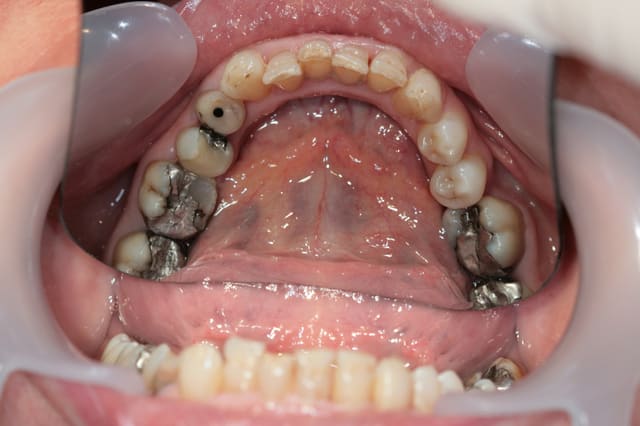

Récemment Céramik râlé, parce qu'il n'y avait pas de nouveau cas (esthétique je crois) à se mettre sous la dent. Je me jettes à l'eau avec ce dernier cas posé ce vendredi (y'a pas plus frais), une larme à l'oeil parce qu'il s'agit aussi du dernier gros cas dans mon cabinet que je quitte cette semaine pour rejoindre ma belle et nos p'tits bouts loin la bas dans le sud.

La patiente a un sourire très médiocre avec migration de plus en plus marqué du bloc incisivocanin sup. Comment l'aidez vous?